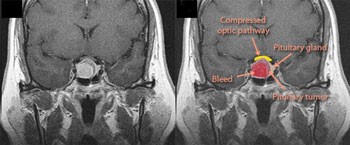

Anaesthesia and pituitary disease

Pituitary gland is a master endocrine gland of the neuro-endocrine axis, having a central role in governing hormonal homeostasis, maintaining the reproductive cycle, and coordinating the activity of other glands. Pituitary disease is common, and a thorough knowledge of the anatomy, physiology, and pathology of the pituitary is required to appropriately manage such patients for surgery<br /> <br />Pituitary apoplexy<br />The term refers to acute haemorrhagic infarction of a gland whose blood supply is previously compromised by a tumour or pregnancy. It can be caused by obstetric haemorrhage (Sheehans syndrome), major surgery, head injury, and sickle cell crisis. It presents as acute failure of anterior lobe function; the posterior lobe function usually being preserved. <br /><br /><br /> Patients with pituitary disease undergoing pituitary or other surgery can present a host of anaesthetic challenges. Anaesthetists must have a good appreciation of the varied presentation of pituitary disease and their implications for the patient's perioperative state. Good communication and teamwork between the neurosurgeon, anaesthetist, neuroendocrine service, and the radiologist is fundamental to the successful management of patients with pituitary disease undergoing surgery.<br /><br />Dr. Sura Awadh